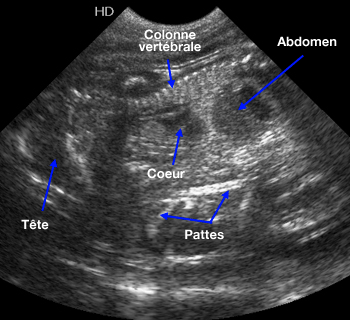

Échographie d'une chatte gestante

(Photo : vetopsy.fr)

6. La gestation commence.